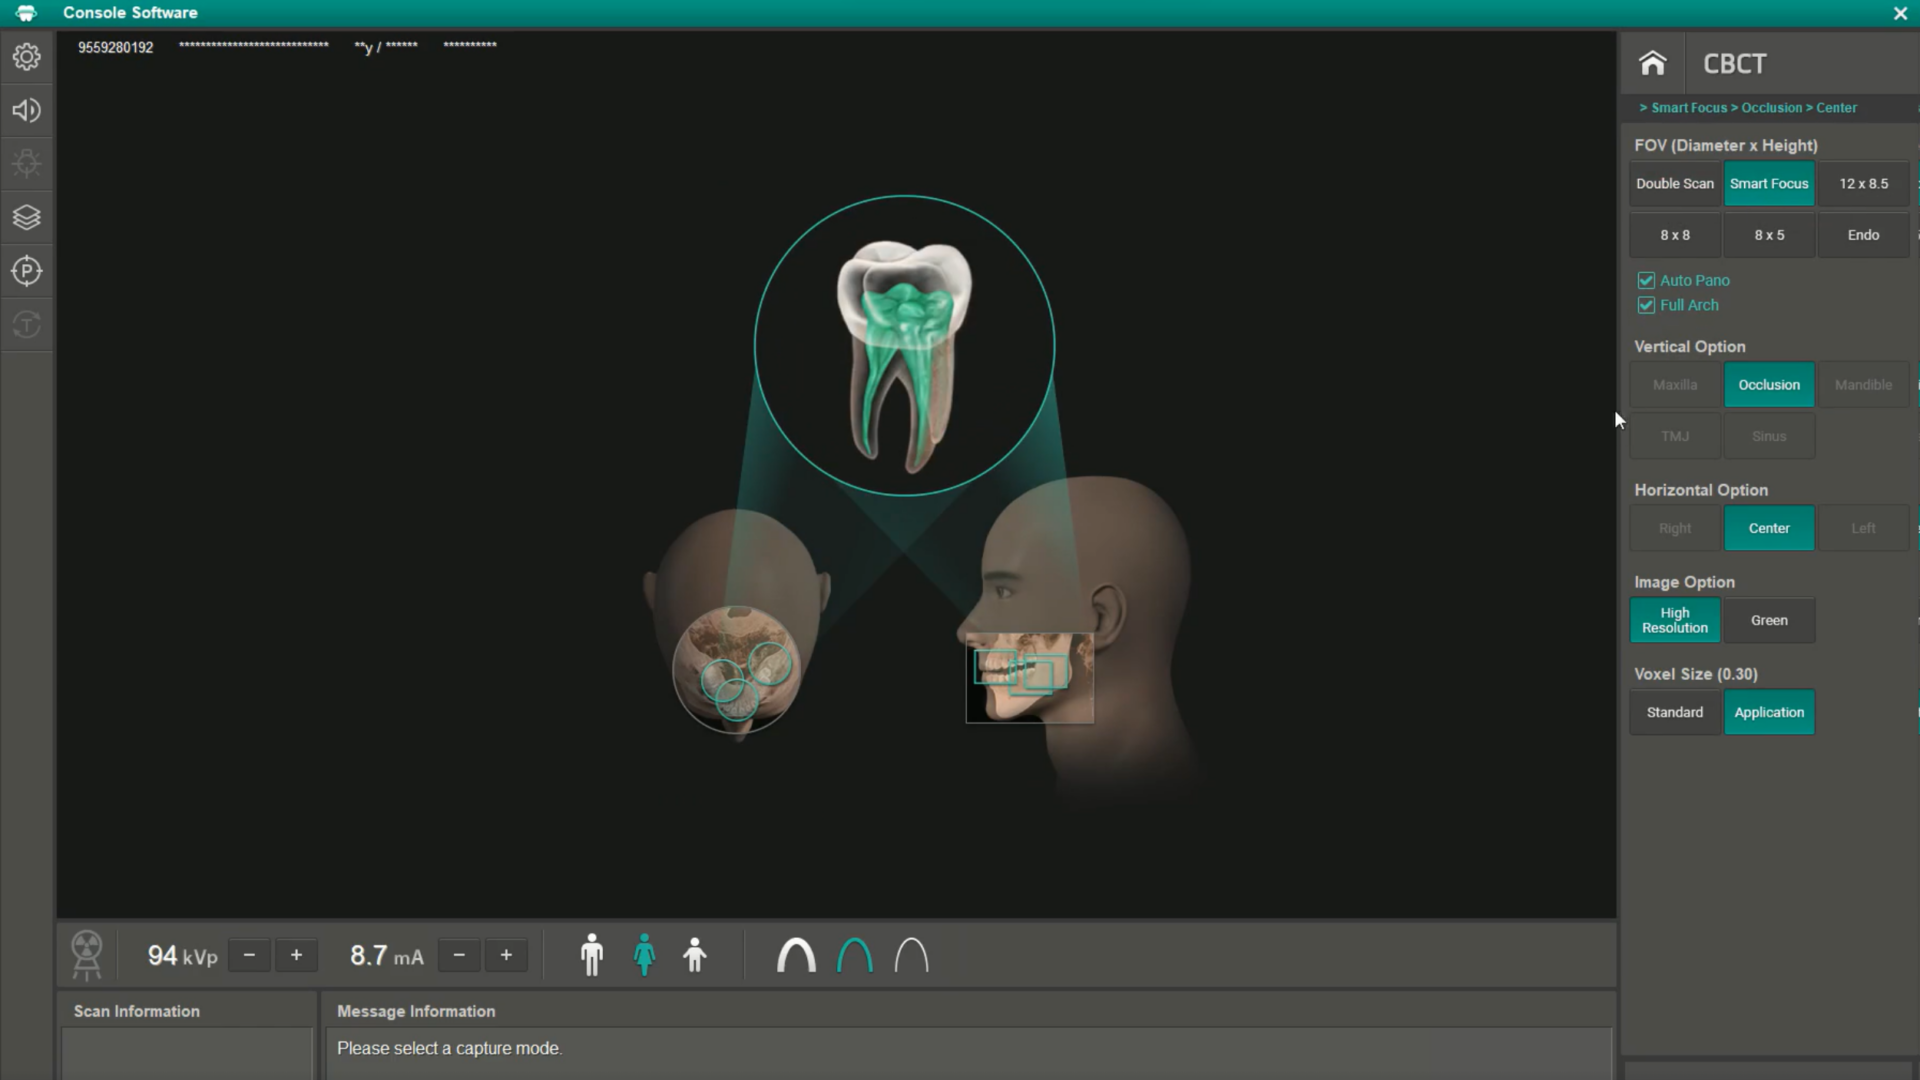

Green X 12 este un sistem 4-în-1 avansat care combină imagistica Cone Beam CT (CBCT), panoramarea, scanarea modelelor 3D (CAD-CAM) și funcții endodontice specializate, oferind o soluție completă pentru diagnostic și tratament în stomatologie.

- SMART FOCUS: 1 scanare, 5 imagini

Cu o singură scanare, Green X 12 generează 5 imagini de înaltă rezoluție: trei imagini de 4×4 cm, o imagine de 12×8,5 cm și o imagine Auto PANO. Acest lucru reduce timpul de muncă pentru personal și minimizează expunerea la radiații pentru pacienți, asigurând un flux de lucru mai eficient și rapid.

- Selectarea Multi-FOV

Dispozitivul oferă 5 opțiuni de câmp vizual (FOV) între 4×4 cm și 12×8,5 cm, toate cu doză redusă. Cu funcția Double Scan, puteți extinde imaginea la 12×14 cm pentru o analiză completă a arcului dentar, inclusiv articulația temporo-mandibulară (ATM).

Specificații tehnice:

- Funcții: CBCT, Pano, Scanare Model 3D

- Dimensiune punct focal: 0,5 mm

- Dimensiuni FOV:

- 4×4 cm (endo, Smart Focus)

- 8×5 cm, 8×8 cm

- 12×8,5 cm (Smart Focus)

- 12×14 cm (Double Scan)

- Dimensiune voxel:

- 0,049 mm (4×4 cm)

- 0,12 mm / 0,2 mm (8×5/8×8 cm)

- 0,2 mm / 0,3 mm (12×8,5 cm)

- 0,3 mm (Double Scan 12×14 cm)

- Timp de scanare:

- Panoramă: 1,4 sec / 13,5 sec

- CBCT: 9 sec / 16,9 sec

- Scala Gray: 14 Bit